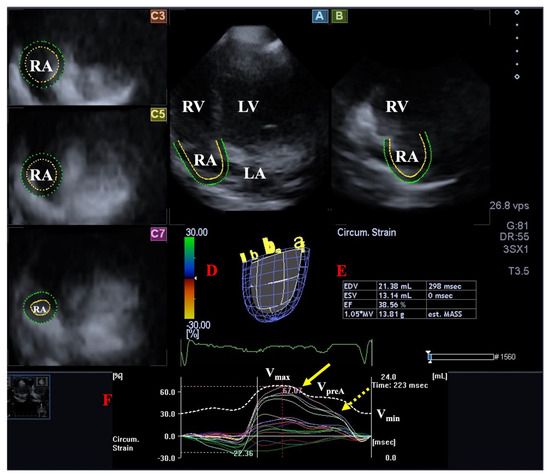

Long-Term Follow-Up of Professional Soccer Players: The Analyses of Left and Right Heart Morphology and Function by Conventional, Three-Dimensional, and Deformation Analyses

Background: Transthoracic echocardiography (TTE) is the primary imaging modality to assess cardiac morphology and function. In athletes, distinguishing physiological adaptations from pathological changes is essential. This study aimed to evaluate long-term cardiac structural and functional changes in professional soccer players. Methods: This retrospective [...] Read more.

Background: Transthoracic echocardiography (TTE) is the primary imaging modality to assess cardiac morphology and function. In athletes, distinguishing physiological adaptations from pathological changes is essential. This study aimed to evaluate long-term cardiac structural and functional changes in professional soccer players. Methods: This retrospective study included 20 healthy male professional soccer players (mean age 21.2 ± 3.4 years) from the German first division, examined annually from 2016 to 2024 (mean follow-up 5.6 ± 2.0 years). TTE parameters associated with the “athlete’s heart” were assessed, including left ventricular end-diastolic diameter (LVEDD), interventricular septal thickness (IVSD), relative wall thickness (RWT), indexed LV mass (LVMi), and left atrial volume index (LAVi), along with 3D-derived LV and RV volumes. Advanced deformation imaging included global longitudinal strain (GLS), right ventricular strain (RVS), and left/right atrial reservoir strain (LASr and RASr, respectively). Baseline and final follow-up values were compared. Results: No significant changes were observed over time in conventional or advanced echocardiographic parameters (e.g., LVEDD: 54.5 ± 3.1 mm vs. 54.6 ± 3.9 mm; p = 0.868; GLS: −18.7% ± 2.2% vs. −18.4% ± 1.9%; p = 0.670). Ventricular volumes and strain values also remained stable throughout follow-up. Conclusions: Over a mean follow-up of more than five years, professional soccer players showed stable cardiac morphology and function without evidence of pathological remodeling. These findings support the concept that long-term high-level training in mixed-discipline sports leads to balanced, physiological cardiac adaptation. Full article

Show Figures

Figure 1